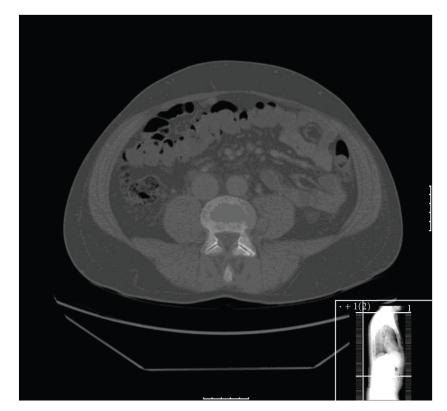

Unlike other soft tissue sarcomas, myxoid/round cell liposarcoma (MRCL) has a tendency to spread to extrapulmonary sites but bone metastases are thought to be uncommon. In case reports, negative bone scintigraphy has been noted in patients with myxoid/round cell liposarcoma and bone metastases but the prevalence and optimal method of diagnosis of bone metastases in this common subtype of liposarcoma are unclear. In an attempt to answer these questions, data were obtained from a prospective database of patients with sarcoma, including MRCL, and the diagnostic imaging used was examined. A variety of imaging tools were used including plain X-rays, bone scintigraphy, computed tomography (CT), and magnetic resonance imaging (MRI). Eight patients (4.3%) developed skeletal metastases all of which were positive on MRI. Bone scintigraphy was negative in two out of four cases, CT was negative in six out of seven, and X-rays were negative in four. Radiography and CT measure mainly cortical bone involvement, whereas MRI examines bone marrow. When investigating patients with MRCL for bone pain, negative X-rays and bone scans do not rule out bone metastases. In our experience, MRI provides the most sensitive technique for the diagnosis of bone metastases in MRCL.

与其他软组织肉瘤不同,黏液样/圆形细胞脂肪肉瘤(MRCL)有扩散至肺外部位的倾向,但骨转移被认为并不常见。在病例报告中,黏液样/圆形细胞脂肪肉瘤伴骨转移的患者骨闪烁扫描结果为阴性,但这种常见脂肪肉瘤亚型中骨转移的发生率及最佳诊断方法尚不清楚。为回答这些问题,我们从一个包括MRCL在内的肉瘤患者前瞻性数据库中获取数据,并对所使用的诊断性影像学检查进行了分析。我们使用了多种影像学工具,包括普通X线、骨闪烁扫描、计算机断层扫描(CT)和磁共振成像(MRI)。8例患者(4.3%)发生了骨转移,所有病例的MRI检查均为阳性。4例中有2例骨闪烁扫描结果为阴性,7例中有6例CT检查结果为阴性,4例X线检查结果为阴性。X线摄影和CT主要检测皮质骨受累情况,而MRI检查骨髓。在对有骨痛的MRCL患者进行检查时,X线和骨扫描结果为阴性并不能排除骨转移。根据我们的经验,MRI是诊断MRCL骨转移最敏感的技术。